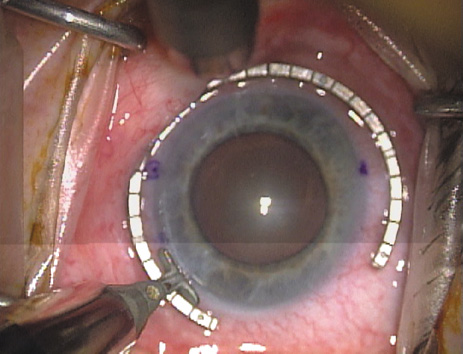

ways. Our preferred method makes use of a modified Fine-Thornton fixation

ring (Nichamin Fixation Ring and Gauge; Mastel Precision, Storz, Rhein

Medical). This instrument serves to fixate and position

the globe in order to optimize incision placement, as well as to delineate

the extent of arc to be incised. One visually extrapolates from

the limbus to marks on the surface of the ring. Each incremental mark

is 10 degrees apart, and bold hash marks (180 degrees) opposite

to each other serve to align and center the incision over the steep

meridian. This approach obviates the need to ink and physically mark

the cornea. If one desires, particularly when first gaining experience

with LRIs, a two-cut RK marker may be used to place ink marks upon the

cornea to show the exact extent of arc that is to be incised, in conjunction

with the fixation ring/gauge (Fig. 4). Alternatively, various press-on markers are available, such as

markers, rings, and blades for performing LRIs.  Fig. 4. The Nichamin Fixation Ring and Gauge serves to both fixate the globe and

delineate the extent of arc to be incised; a two-cut radial marker may

be used to mark the extent of arc to be incised, and the Mastel Nichamin

Force AK Diamond Blade with preset depth of 600 microns. Fig. 4. The Nichamin Fixation Ring and Gauge serves to both fixate the globe and

delineate the extent of arc to be incised; a two-cut radial marker may

be used to mark the extent of arc to be incised, and the Mastel Nichamin

Force AK Diamond Blade with preset depth of 600 microns.